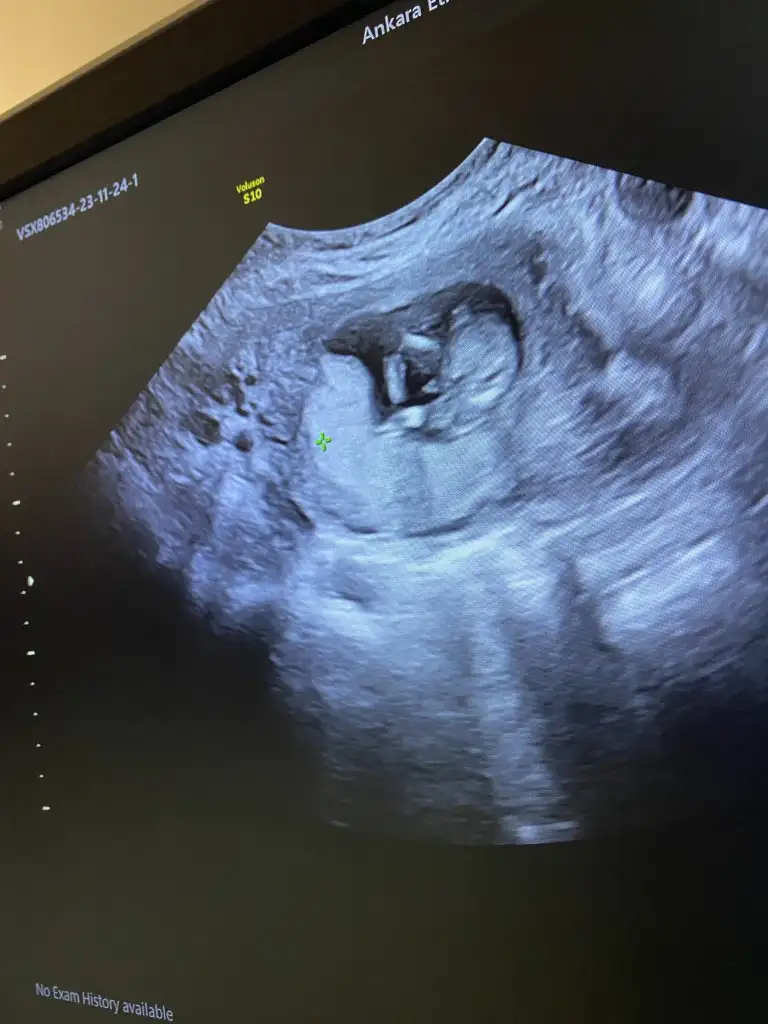

merhabalar 18 haftalik hamileyim doktorum kordon önüne geliyor emin değilim dedi tahminim erkek dedi sizce nedir çok merak ediyorum bakar mısınız?

Bacak Arası ilk kız demişlerdı BNde kız olarak görmüştüm alttan bugün böyle gördük sızce kordon mu pipi mi

Kaç haftaliksiniz? Ortadaki çıkıntı çok top gibi duruyor ve çok yukarıda birde büyük duruyor bebeğin pozisyonuna göre. Eğer haftasına göre gelişiyorsa tam pipiye benzememiş mi desem bilemedim belki de sivrileşecektir. Doktor bu cikintiya erkek mi dedi bugün? Eğer dediyse net erkektir çünkü çıkıntı pipi olma ihtimali yüksek oluyor